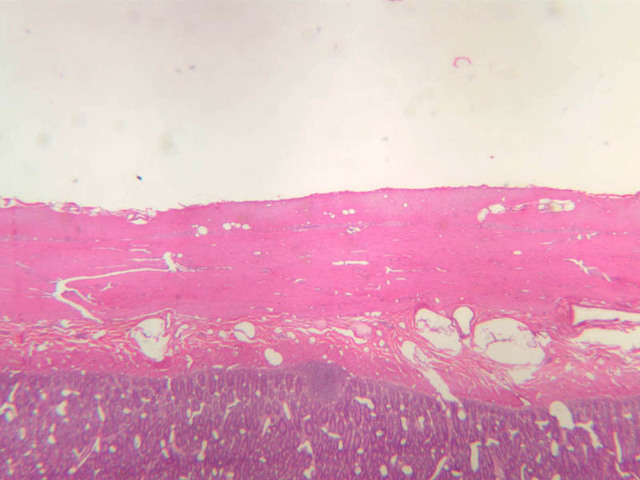

The blood is pumped from the heart into large, elastic (conduction) arteries. Examine a section of the aorta (A-26, H&E [2.5x, 10x, 20x, 40x-labeled] [2.5x, 10x-labeled, 20x, 40x]) which is a typical elastic artery. Although the tunica intima and tunica media are difficult to distinguish, note that together they are much thicker than the tunica adventitia. Using high power magnification, examine the tunica media and identify the cell types and fibers, recalling that elastic tissue appears light pink and refractive in H&E preparations. Compare this slide with a section of aorta stained to demonstrate elastic fibers (A-27, verhoeff [2.5x, 10x, 20x, 40x-labeled] [2.5x, 10x]).

Note how extensive the elastic tissue is in the tunica media. The elastic tissue is arranged in the form of numerous concentric elastic lamellae, which are cross connected by slender elastic fibers. Observe the distribution of elastic fibers in the tunica intima (A- 27 [2.5x, 10x, 20x, 40x]) and tunica adventitia (A-27 [10x, 20x, 40x]). The internal and external elastic membranes are not well demarcated in the aorta since so many elastic lamellae are present. The elasticity of the aorta allows it to expand and absorb much of the pressure during contraction of the left ventricle (i.e., systole). When the ventricle relaxes (diastole), the elastic aorta contracts, continuing the movement of blood into the medium and muscular arteries.